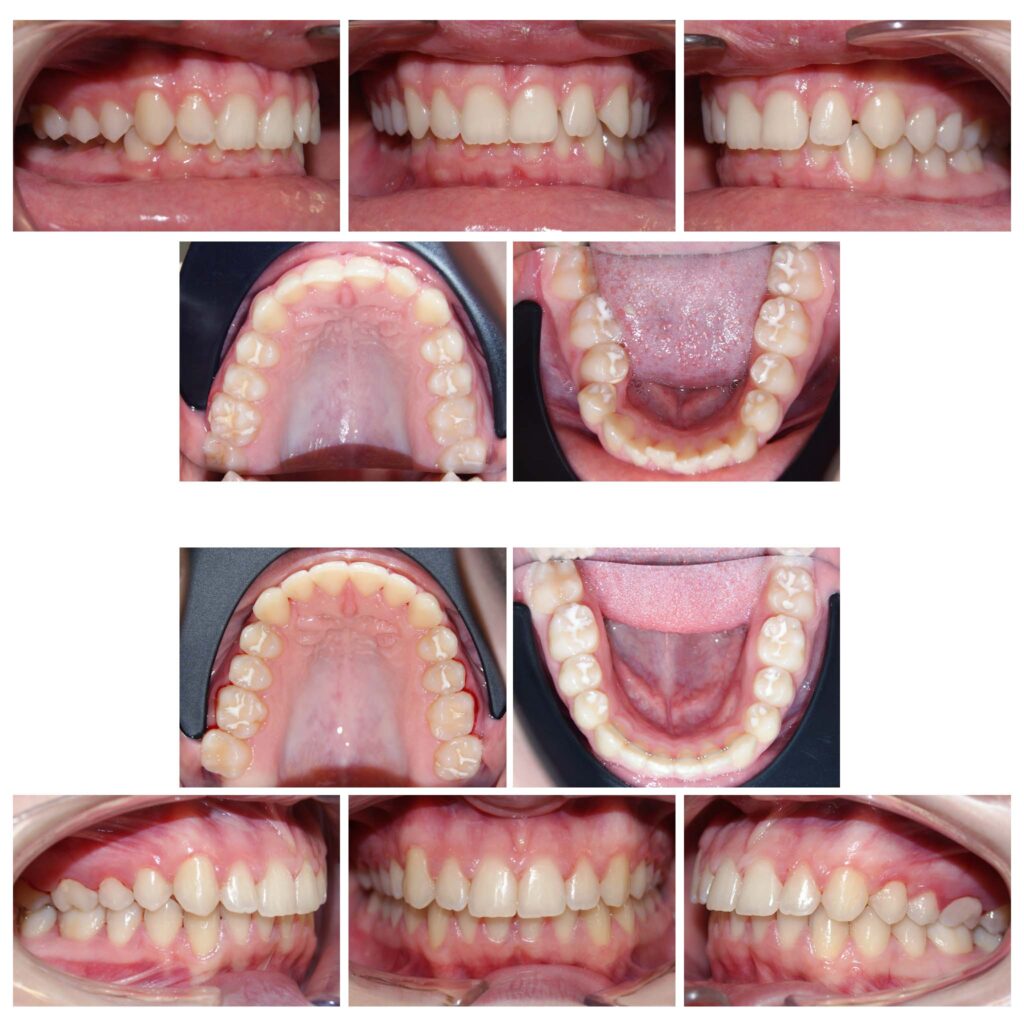

În cazul de față ortodonția ne-a ajutat să oferim lărgime semnificativă zâmbetului și să prevenim retracțiile gingivale de pe caninii inferiori prin distalizare.